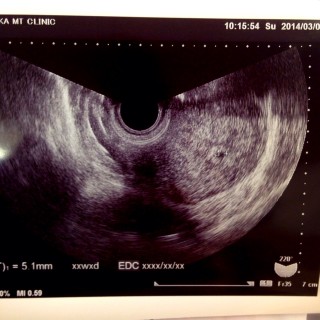

3人目の妊娠です!上が5歳、下が1歳です。下の子がなかなかできず、治療しやっと授かった子でした。しかし今回自然妊娠し、驚きとともに喜びでいっぱいですo(^▽^)o 妊娠の知識も多少あるので、今回初めての検診で5mmの胎嚢が少し小さいなーっと感じ不安になっています。 でも、わたしはこの子を信じます。 パパもママもお兄ちゃんたちもあなたに会える日を待ち望んでいるよ!元気に産まれておいで!